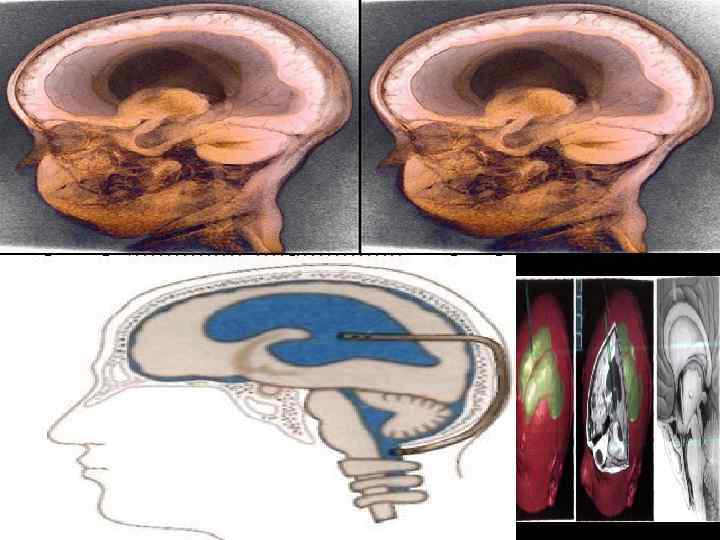

Наружное дренирование желудочков мозга по Арендту Вентрикулоцистернальное дренирование по Торкильдсену 98

Вентрикулоперитонеальное шунтирование 99